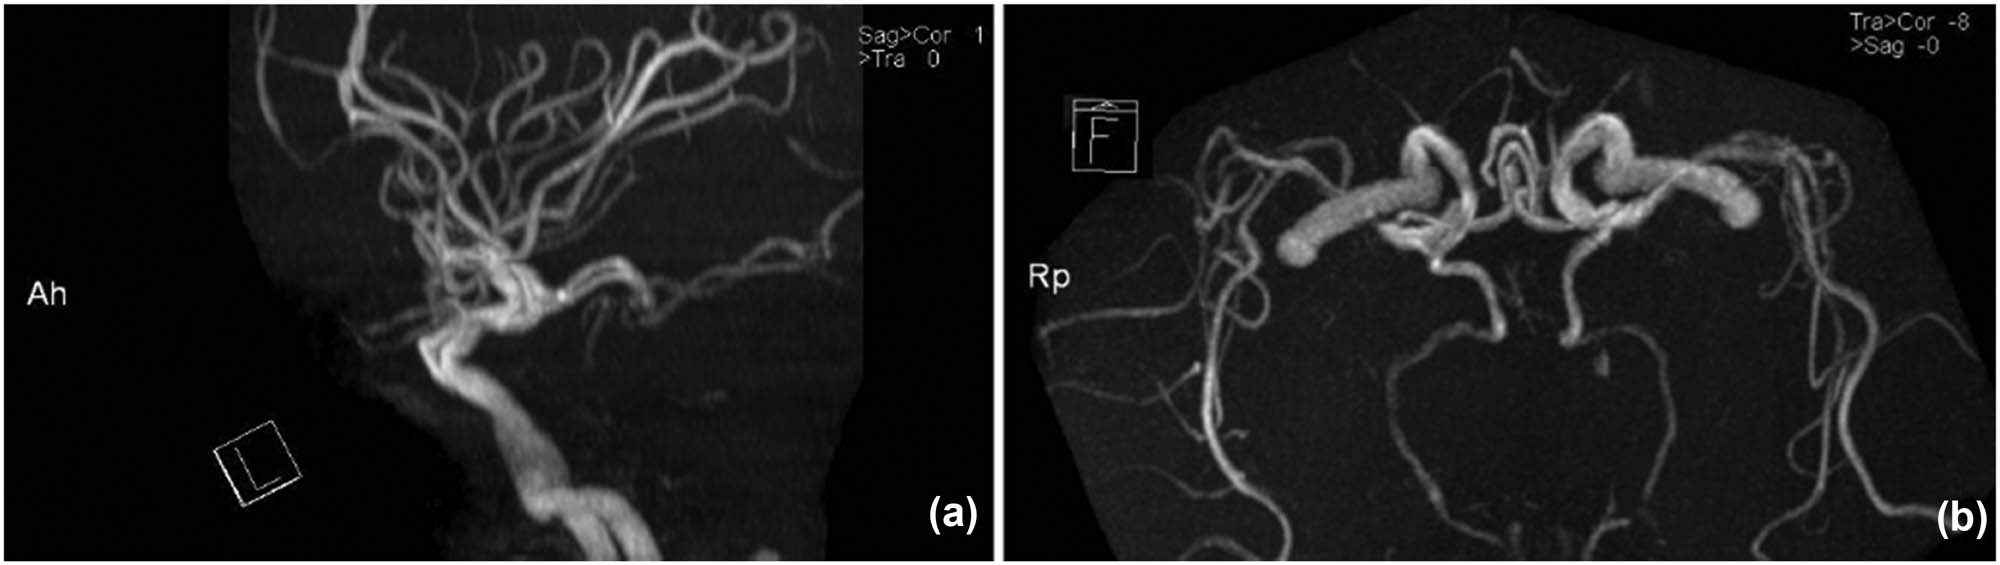

Brain magnetic resonance angiography (MRA) showed atherosclerosis of the bilateral internal carotid artery (ICA) throughout the entire length. The outlines of the vertebral-basilar system (VBS) were irregular and vague, with its lumen diameter <2 mm. Both the posterior cerebral arteries (PCA) were originated from a posterior communicating artery (PCoA) separately, which were considered as a fetal-type posterior cerebral artery (FTP) variation (Figure 2a and b). Meanwhile, the anterior spinal artery (ASA) was not visualized. There is no apparent dissection of the vertebral arteries (VA). The option of digital subtraction angiography (DSA) and endovascular approach was offered to his relatives, but his wife refused both.

(TOF-MRA imaging): the lateral projection of an MRA image shows the hypoplastic BAS. (a and b) The posterior communicating arteries supply the territory of all branches of the PCAs, which were considered as fetal-type. (b) Caudocranial projection image shows that both PCAs were divided from ICA separately.